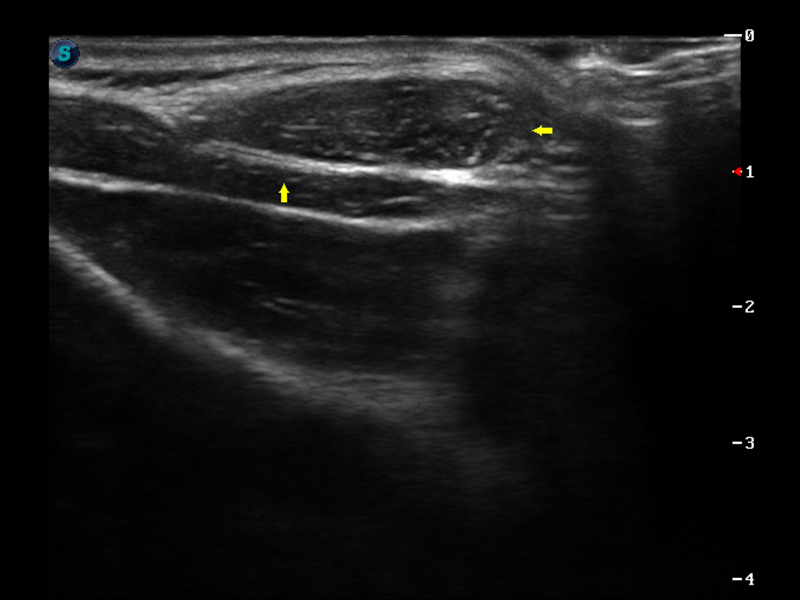

弹性成像